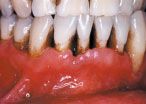

It is well known in the dental community that the emergence of the HIV infection in the early 1980s was accompanied by an explosion of some common and some rarer oral conditions including candida infections, Kaposi’s sarcoma, hairy leukoplakia, and a variety of other bacterial infections. In addition, HIV-associated infections associated with the periodontium included a linear gingival erythema (Fig. 3), necrotizing gingivitis (Fig. 4), human papilloma virus, and most seriously a necrotizing periodontitis with both soft- and hard-tissue necrosis that could extend beyond the periodontal tissues (Figs. 5-7).

While candida infections often were an early indicator of HIV infection and the beginning of the decline in immune status, necrotizing periodontitis in these patients was usually an indication of a severe decline in immune function and marked increase in the HIV viral load as the patient progressed to full-blown AIDS. However, with the advent in the early 1990s of a combination of antiretroviral drugs and new antiviral approaches known as HAART (Highly Active Antiretroviral Therapy), there was a marked decline (and in some cases a near complete disappearance) of some of these more serious oral/periodontal lesions, as viral levels remained suppressed and immune function was preserved.

In addition, HIV patients can still present with signs of chronic periodontitis (Fig. 8). However, more recently, in several populations and geographical areas, these more serious oral lesions in HIV lesions have begun to reemerge.